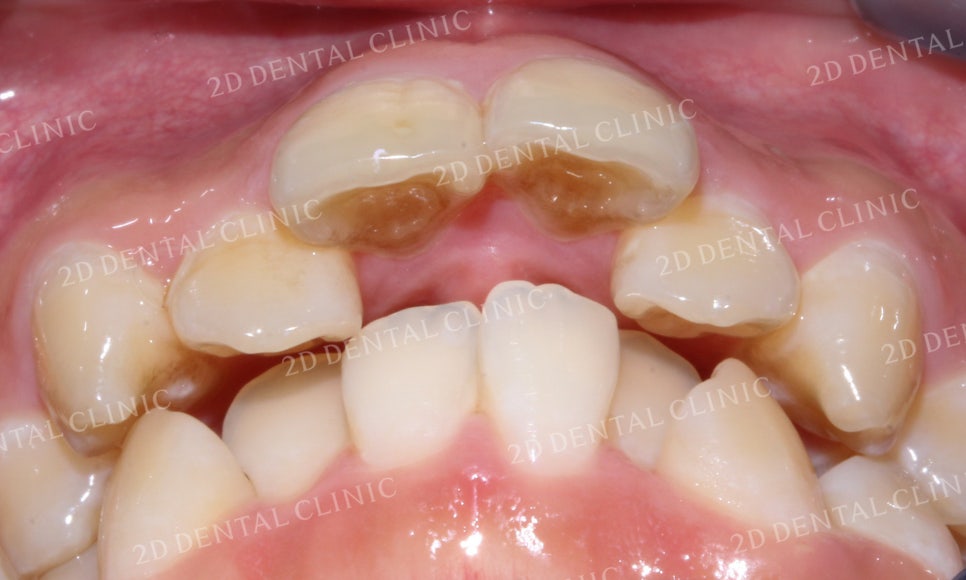

전치부 치아를 자세히 살펴보면

상악의 중절치가 돌출되어 있는 상태입니다.

상악의 돌출된 중절치의 뒤쪽으로 측절치가

파고들어 맹출 된 상태로 교정 후 치열이

고르게 바뀌면서 치간이개로 인한

블랙트라이앵글이 발생할 수 있습니다.

하악의 전치부 역시 크라우딩이 심한 상태로

교정 후 블랙트라이앵글 발생 가능성이 높습니다.